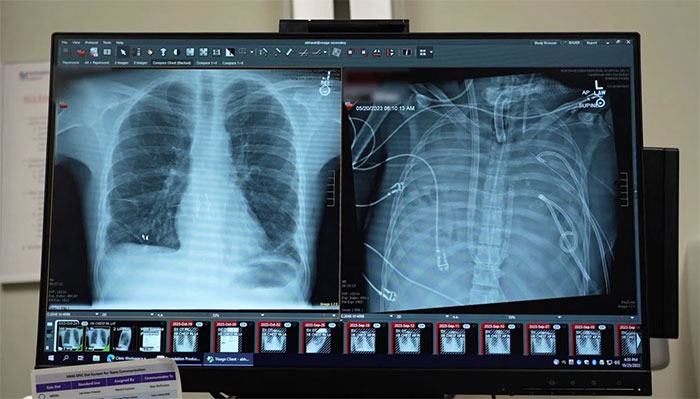

Trong nghiên cứu đăng trên tạp chí khoa học Med (thuộc Cell Press), các bác sĩ phẫu thuật mô tả cách họ loại bỏ hoàn toàn hai lá phổi bị nhiễm trùng nghiêm trọng của bệnh nhân, sau đó duy trì sự sống cho anh bằng một hệ thống “phổi nhân tạo” tự thiết kế cho đến khi tìm được phổi hiến tặng phù hợp. Nhóm nghiên cứu cho rằng phương pháp này có thể trở thành “cầu nối” cứu sống những bệnh nhân có nguy cơ tử vong khi chờ ghép tạng.

Bệnh nhân là một người đàn ông 33 tuổi mắc hội chứng suy hô hấp cấp tính (ARDS) – tình trạng viêm và nhiễm trùng dữ dội khiến phổi bị tràn dịch và mất chức năng. Căn bệnh bắt đầu từ cúm, sau đó nhanh chóng trở nặng do viêm phổi do vi khuẩn.

Khi phổi suy kiệt, tim và thận của anh cũng bắt đầu suy theo. Các bác sĩ kết luận ghép hai lá phổi là cơ hội sống sót thực tế duy nhất. Tuy nhiên, tình trạng cơ thể lúc đó quá bất ổn để có thể tiến hành ghép ngay lập tức. Cơ thể cần thời gian hồi phục trước khi tiếp nhận tạng mới.

Sau khi hai lá phổi nhiễm trùng được loại bỏ, tình trạng bệnh nhân bắt đầu cải thiện rõ rệt. Huyết áp ổn định trở lại, các cơ quan khác dần phục hồi chức năng và nhiễm trùng được kiểm soát. Hai ngày sau, nhóm tìm được phổi hiến phù hợp và tiến hành ca ghép kép thành công.

Phân tích chuyên sâu các lá phổi bị cắt bỏ cho thấy mô phổi đã xơ hóa nghiêm trọng và chịu tổn thương miễn dịch ở mức độ cao. Các xét nghiệm phân tử xác nhận tổn thương đã vượt quá khả năng tự chữa lành.